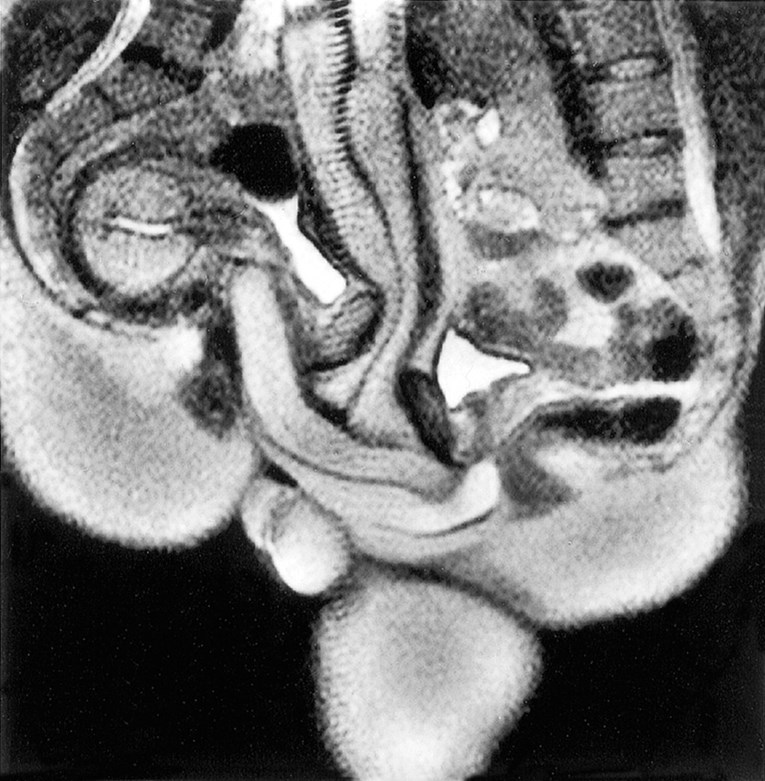

PAR KOJI je imao spolni odnos unutar uređaja za magnetsku rezonancu (MR) u sklopu znanstvenog eksperimenta uspio je zauvijek promijeniti naše razumijevanje ljudske anatomije. Iako se znanost često prikazuje kroz stereotipe o laboratorijima i kemikalijama, neki su eksperimenti, poput ovoga, u najmanju ruku neobični, ali su njihovi rezultati bili revolucionarni.

Rezultati, objavljeni tek 1999. godine u časopisu British Medical Journal, pokazali su da je “snimanje magnetskom rezonancom muških i ženskih genitalija tijekom koitusa izvedivo i doprinosi razumijevanju anatomije”.

Studija je otkrila ključne detalje. “Dobivene slike pokazale su da tijekom spolnog odnosa u misionarskom položaju penis ima oblik bumeranga i da se 1/3 njegove duljine sastoji od korijena penisa”, navodi se u radu. Također je utvrđeno da je “tijekom ženskog seksualnog uzbuđenja bez spolnog odnosa maternica bila podignuta, a prednja stijenka rodnice produljena. Veličina maternice nije se povećala tijekom seksualnog uzbuđenja.”